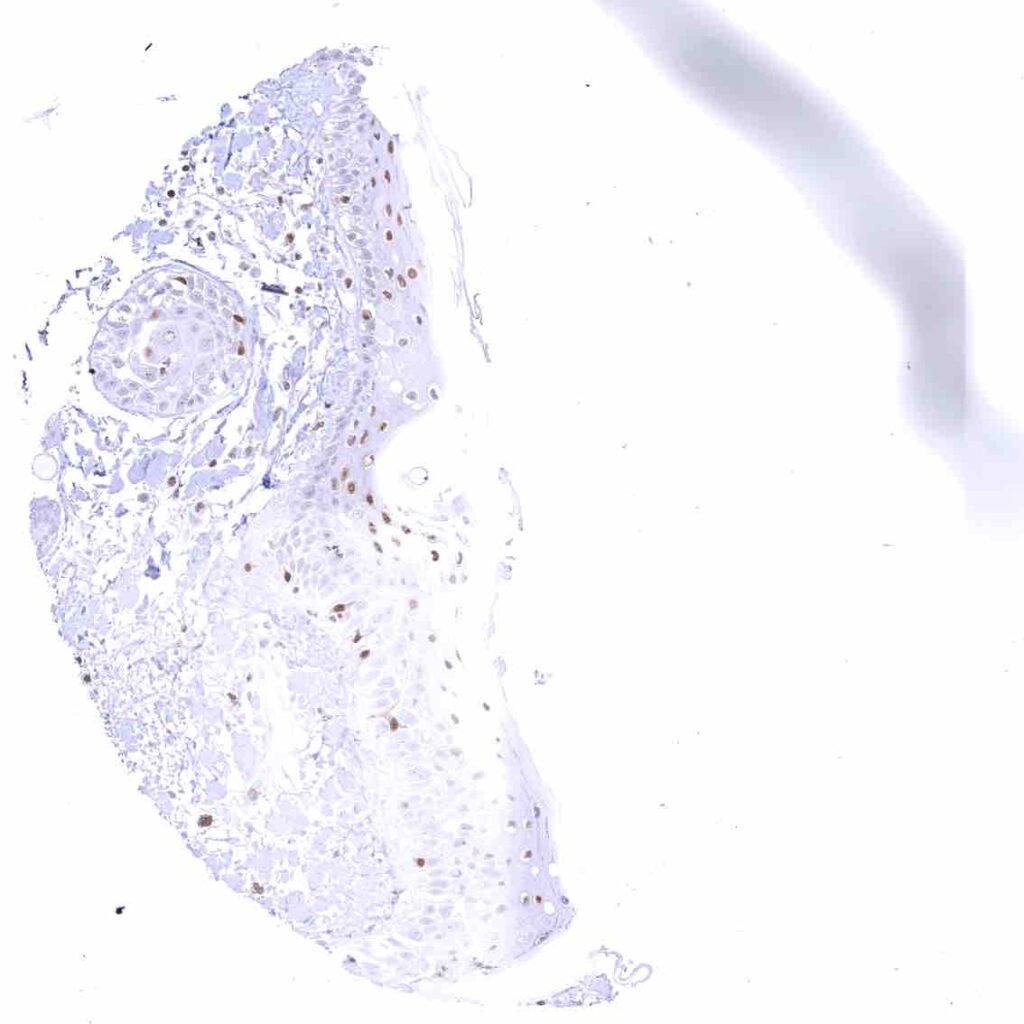

Skin – Moderate to strong nuclear p27 staining occurs in a large fraction of squamous epithelial cells and predominates in the more mature cell layers (top 50_ of the epidermis).

Skin, hairfollicel and sebaceous glands – Moderate to strong nuclear p27 staining in all cells of sebaceous glands. .jpeg

Uterus, ectocervix – Nuclear staining of squamous epithelial cells predominates in the more mature cell layers (top 50_ of the epidermis).